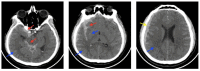

Cerebral edema is the abnormal accumulation of fluid in any of the tissue compartments of the cerebral parenchyma. It remains a significant challenge in neurotrauma care because it contributes to secondary brain injury, affecting prognosis. This review analyzes the recent literature, including foundational studies, to describe the mechanisms of distinct types of cerebral edema following traumatic brain injury (TBI). Emerging concepts, such as the role of the glymphatic system and heme-derived inflammasomes, offer new insights into new types of edemas, differentiated by pathogenesis and potential treatments. Recent advancements in understanding these molecular mechanisms can improve therapeutic strategies, facilitating a better approach in the era of precision and personalized medicine. Although there has been notable progress, a proposal to customize treatments for diverse types of edemas is necessary to improve outcomes following traumatic brain injury. In this review, we describe the current subtypes of post-traumatic brain edemas and link them to a specific management approach.